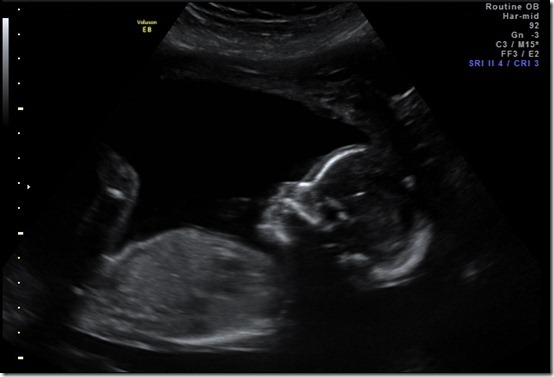

Appointment Summary: I had my OB appointment on Thursday and everything looks great! The heartbeat was right on target and the baby is measuring right where it should be! Yesterday was my big 2nd trimester ultrasound! We were able to see the baby moving around in there! It was pretty amazing to witness and I got a little teary-eyed watching it! Its heart was beating strong and he/she was practicing swallowing which is great for development. ![]()

Right now, my little baby weighs 12 ounces!